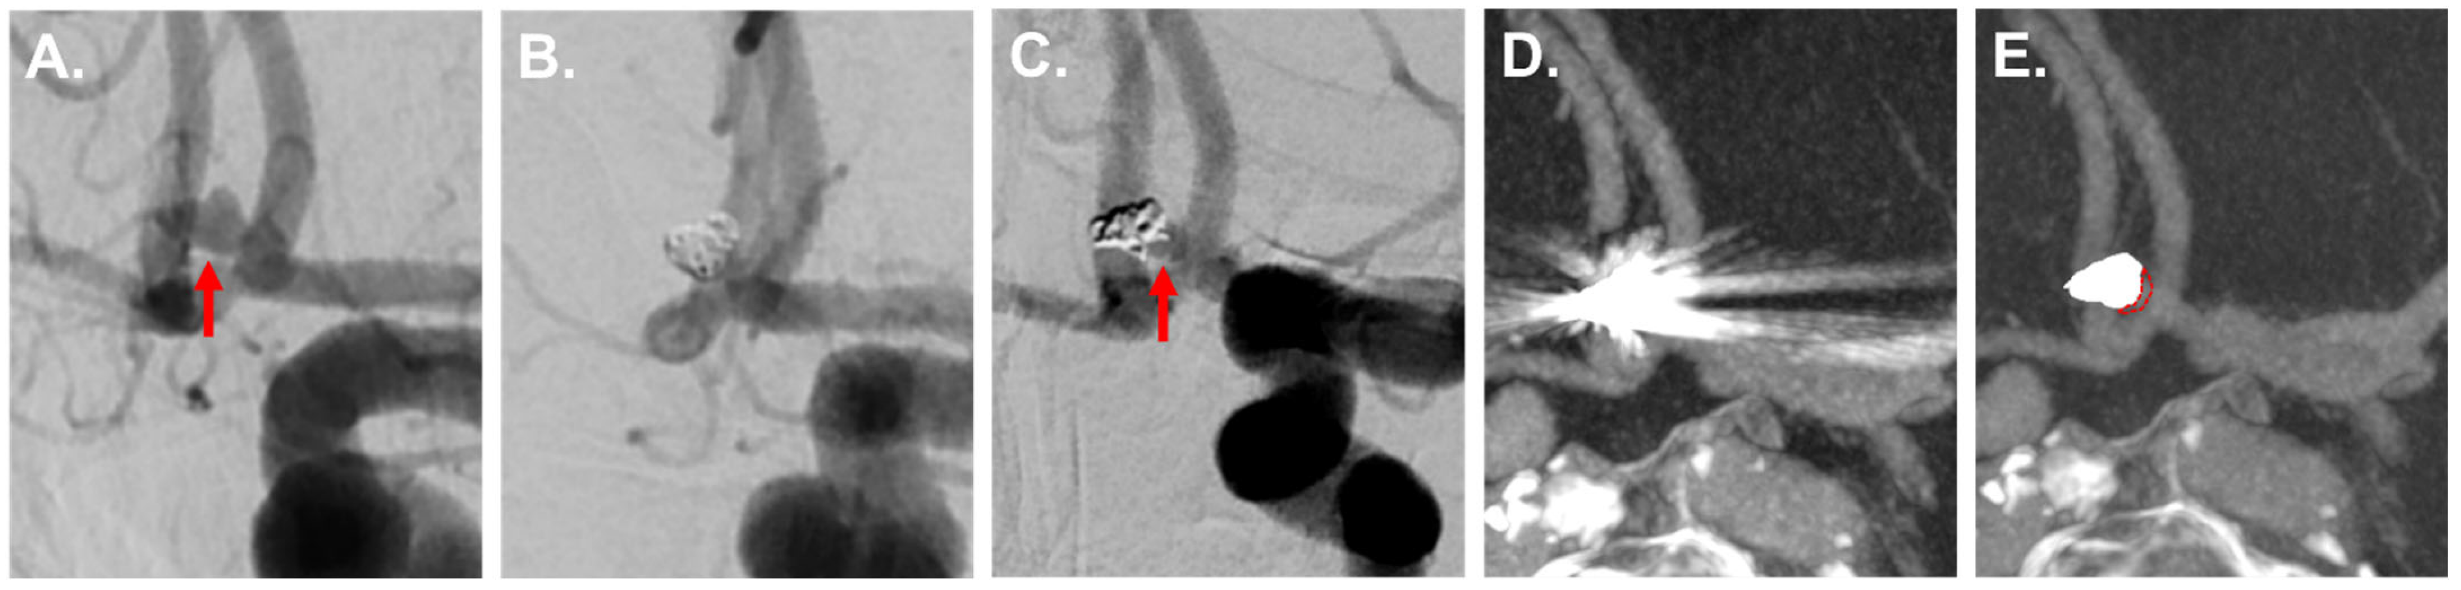

Figure 2, Figure 3 and Figure 4 show exemplary images of DSA data and the corresponding iMAR−/iMAR+ FD-CTA of both patients with IAs treated via endovascular coiling and intracranial clipping.

Figure 3. An 84-year-old patient with an aneurysm of the anterior communicating artery in the initial DSA ((A) red arrow) with consecutive treatment via endovascular coiling (B). Six months later, DSA control revealed a reperfusion at the aneurysm base ((C) red arrow). The aneurysm was not assessable in iMAR− FD-CTA due to severe metal artifacts (D). Thanks to a significant metal artifact reduction, iMAR+ FD-CTA also demonstrated the basal aneurysm reperfusion in accordance with the DSA ((E) marked with red dotted line).